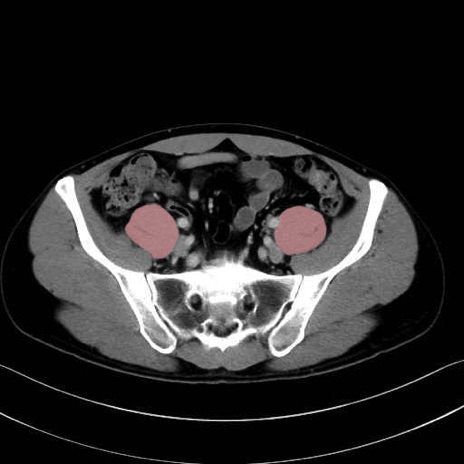

2. 腸腰筋群と骨盤底筋

大腰筋 (Psoas major)

腸骨筋 (Iliacus)